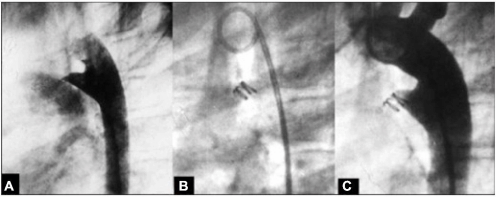

Na figura abaixo, observa-se uma oclusão de ducto arterioso. A: Canal arterial tipo A de 2 mm (milímetros) de diâmetro; B: Configuração helicoidal do dispositivo com uma alça na artéria pulmonar e duas alças na ampola aórtica; C: A ortografia de controle, evidenciando oclusão total.

Qual alternativa apresenta o dispositivo de oclusão utilizado.